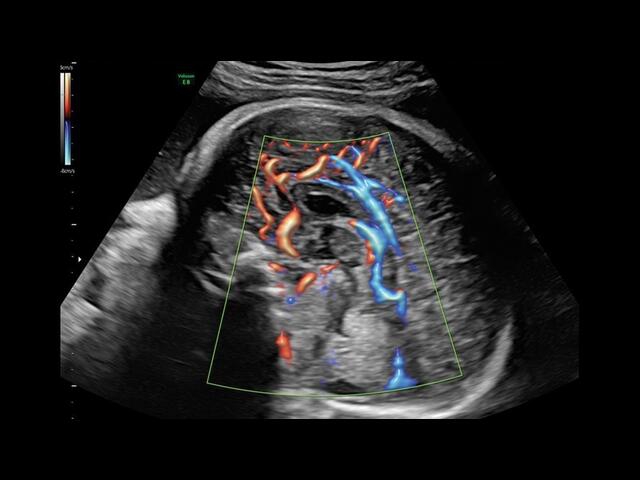

Система GE Voluson E8 обладает значительной вычислительной мощностью, которая позволяет решать даже самые сложные задачи в области диагностики плода. Она отличается высоким уровнем качества и статусом, предоставляя врачу потрясающие изображения во время 2D/3D-исследований. Кроме того, система всегда готова к использованию режима 4D благодаря чувствительному цветному доплеру.

• HD-FlowTM для точного изучения кровотока и прорисовки сосудов.